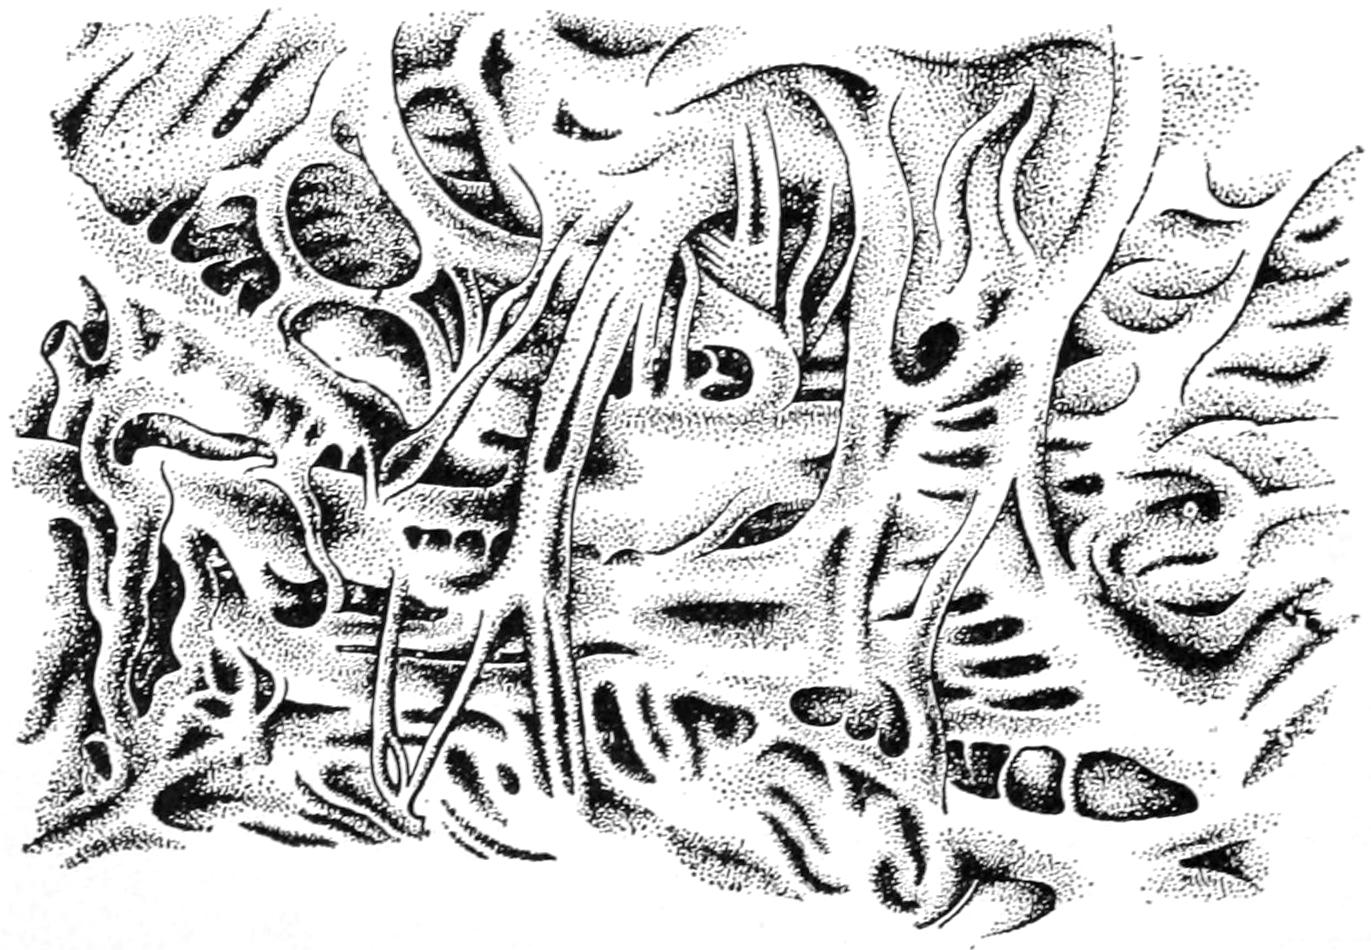

PLATE I

Fig. I.

Fig. II.

Fig. III.

Fig. IV.

Fig. V.

Fig. VI.

Fig. VII.

Fig. VIII.

DRAWN BY J. N. Z. CHASE

PLATE I.

BLOOD.

(Ehrlich triple stain.)

(Prepared by Dr. I. P. Lyon.)

Fig. I. TYPES OF LEUCOCYTES.

a. Polymorphonuclear Neutrophile. b. Polymorphonuclear Eosinophile. c. Myelocyte (Neutrophilic). d. Eosinophilic Myelocyte. e. Large Lymphocyte (large Mononuclear). f. Small Lymphocyte (small Mononuclear).

Fig. II. NORMAL BLOOD.

Field contains one neutrophile. Reds are normal.

Fig. III. ANÆMIA, POST-OPERATIVE (secondary).

The reds are fewer than normal, and are deficient in hæmoglobin and somewhat irregular in form. One normoblast is seen in the field, and two neutrophiles and one small lymphocyte, showing a marked post-hæmorrhagic anæmia, with leucocytosis.

Fig. IV. LEUCOCYTOSIS, INFLAMMATORY.

The reds are normal. A marked leucocytosis is shown, with five neutrophiles and one small lymphocyte. This illustration may also serve the purpose of showing the leucocytosis of malignant tumor.

Fig. V. TRICHINOSIS.

A marked leucocytosis is shown, consisting of an eosinophilia.

Fig. VI. LYMPHATIC LEUKÆMIA.

Slight anæmia. A large relative and absolute increase of the lymphocytes (chiefly the small lymphocytes) is shown.

Fig. VII. SPLENO-MYELOGENOUS LEUKÆMIA.

The reds show a secondary anæmia. Two normoblasts are shown. The leucocytosis is massive. Twenty leucocytes are shown, consisting of nine neutrophiles, seven myelocytes, two small lymphocytes, one eosinophile (polymorphonuclear) and one eosinophilic myelocyte. Note the polymorphous condition of the leucocytes, i. e., their variations from the typical in size and form.

Fig. VIII. VARIETIES OF RED CORPUSCLES.

a. Normal Red Corpuscle (normocyte). b, c. Anæmic Red Corpuscles. d-g. Poikilocytes. h. Microcyte. i. Megalocyte. j-n. Nucleated Red Corpuscles. j, k. Normoblasts. l. Microblast. m, n. Megaloblasts.

The value of a careful blood examination is well illustrated by Plate I, prepared by Dr. Irving P. Lyon, in which are displayed the alterations of greatest interest to the surgeon.